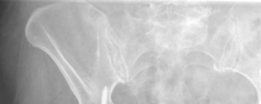

Standard antero-posterior and cross-table lateral radiographs of the pelvis and left hip were obtained immediately following the primary clinical assessment.

The initial AP pelvis radiograph clearly demonstrated a displaced left femoral neck fracture. The fracture line was entirely intracapsular. The femoral head was superiorly and posteriorly displaced relative to the femoral neck, with evidence of approximately 1.5 cm of shortening. The bone quality appeared reasonable for the patient's age, with a preserved Singh index and cortical thickness in the diaphyseal region, though some osteopenia was evident in the proximal trabecular patterns. No signs of pre-existing significant hip osteoarthritis (such as joint space narrowing, subchondral sclerosis, or osteophytosis) in the ipsilateral joint were noted. The contralateral hip appeared unremarkable.

Further radiographic views confirmed the complete displacement and the lack of cortical contact between the proximal and distal fragments. The fracture was classified as a Garden Type IV, indicating complete displacement with a loss of trabecular alignment between the femoral head and the acetabulum, where the head has rotated independently of the neck. Furthermore, it was classified as a Pauwels Type III, meaning the fracture line angle was greater than 70 degrees from the horizontal. This vertical fracture orientation indicates extremely high shear forces across the fracture site, portending a very poor prognosis for osteosynthesis and a high risk of nonunion or fixation failure if internal fixation were to be attempted.